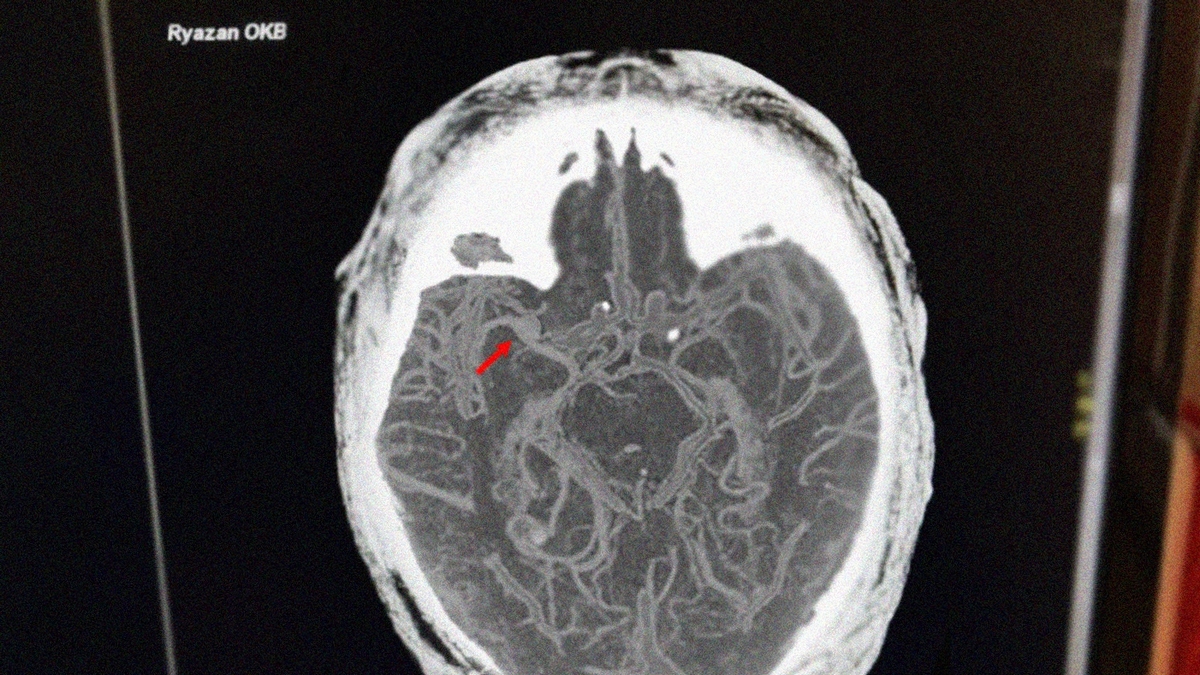

Врачи Рязанской областной клинической больницы спасли 92-летнего мужчину, у которого случился инсульт на остановке. Об этом сообщила пресс-служба больницы.

Пенсионер почувствовал себя плохо, пока ждал транспорт. В больнице пациенту провели процедуру тромболизиса – процедуру провели в установленные сроки. После курса реабилитации мужчину в удовлетворительном состоянии выписали домой.

Фото: министерство здравоохранения Рязанской области